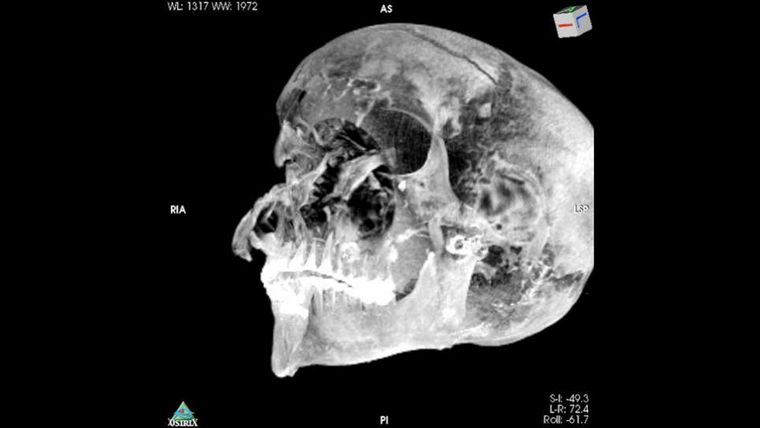

Seqenenre no presentaba daños extremos en su cuerpo, pero su cabeza y rostro estaban seriamente comprometidos. La masiva fractura en su frente fue causada por algo de mucho peso como un hacha, probablemente, desde una posición por encima del faraón.

En la actualidad, un equipo de científicos, dirigido por Sahar Saleem, profesor de radiología en la Universidad de El Cairo, realizó tomografías para volver a analizar la momia, conservada en el Museo Egipcio de El Cairo. El nuevo estudio dejó ver que la momia está en muy mal estado. La cabeza desconectada del cuerpo, vértebras y costillas sueltas, y muy poco tejido blando.